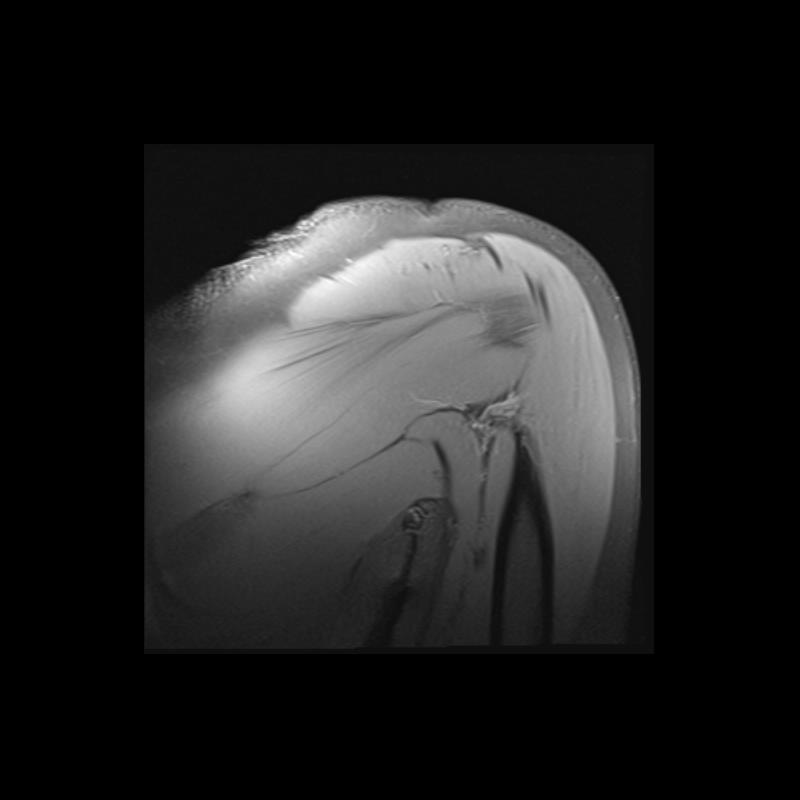

Shoulder MRI Anatomy